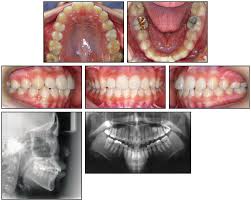

Orthodontictraction Of Impacted Maxillary Canine And Piggyback Techni

Orthodontictraction Of Impacted Maxillary Canine And Piggyback Techni from image.slidesharecdn.com

Patients perception of recovery after exposure of impacted teeth: The difference in time required for the two techniques was statically significant (p = 0.000). The closed technique and the open technique. This facilitates eruption and orthodontic traction. Closed eruption technique for surgical exposure 3 surgical approach can be used 1. The postoperative recovery was longer after open eruption than close eruption technique (p = 0.000). It also can maintain adjacent tooth structure while retaining the option for future implant reconstruction. (1) window technique, (2) full flap open procedure, and (3) apically repositioned flap technique.

Natural autonomous eruption and forced eruption under orthodontic traction. Postoperative pain experienced by patients was similar, but regression of pain was faster in closed eruption technique. Forced eruption can preserve the natural root system and related periodontal architecture, resulting in years of additional service for the patient. It also can maintain adjacent tooth structure while retaining the option for future implant reconstruction. The postoperative recovery was longer after open eruption than close eruption technique (p = 0.000). 26,27 in the case shown here, closed eruption was chosen for the impacted central and. Dr vanarsdall recommends open exposure with a repositioned gingival flap (pediculated connective tissue graft) above the impacted canine. Management of unerupted maxillary incisors 6 5.4 incisor removal 5.5 ankylosed maxillary incisors.